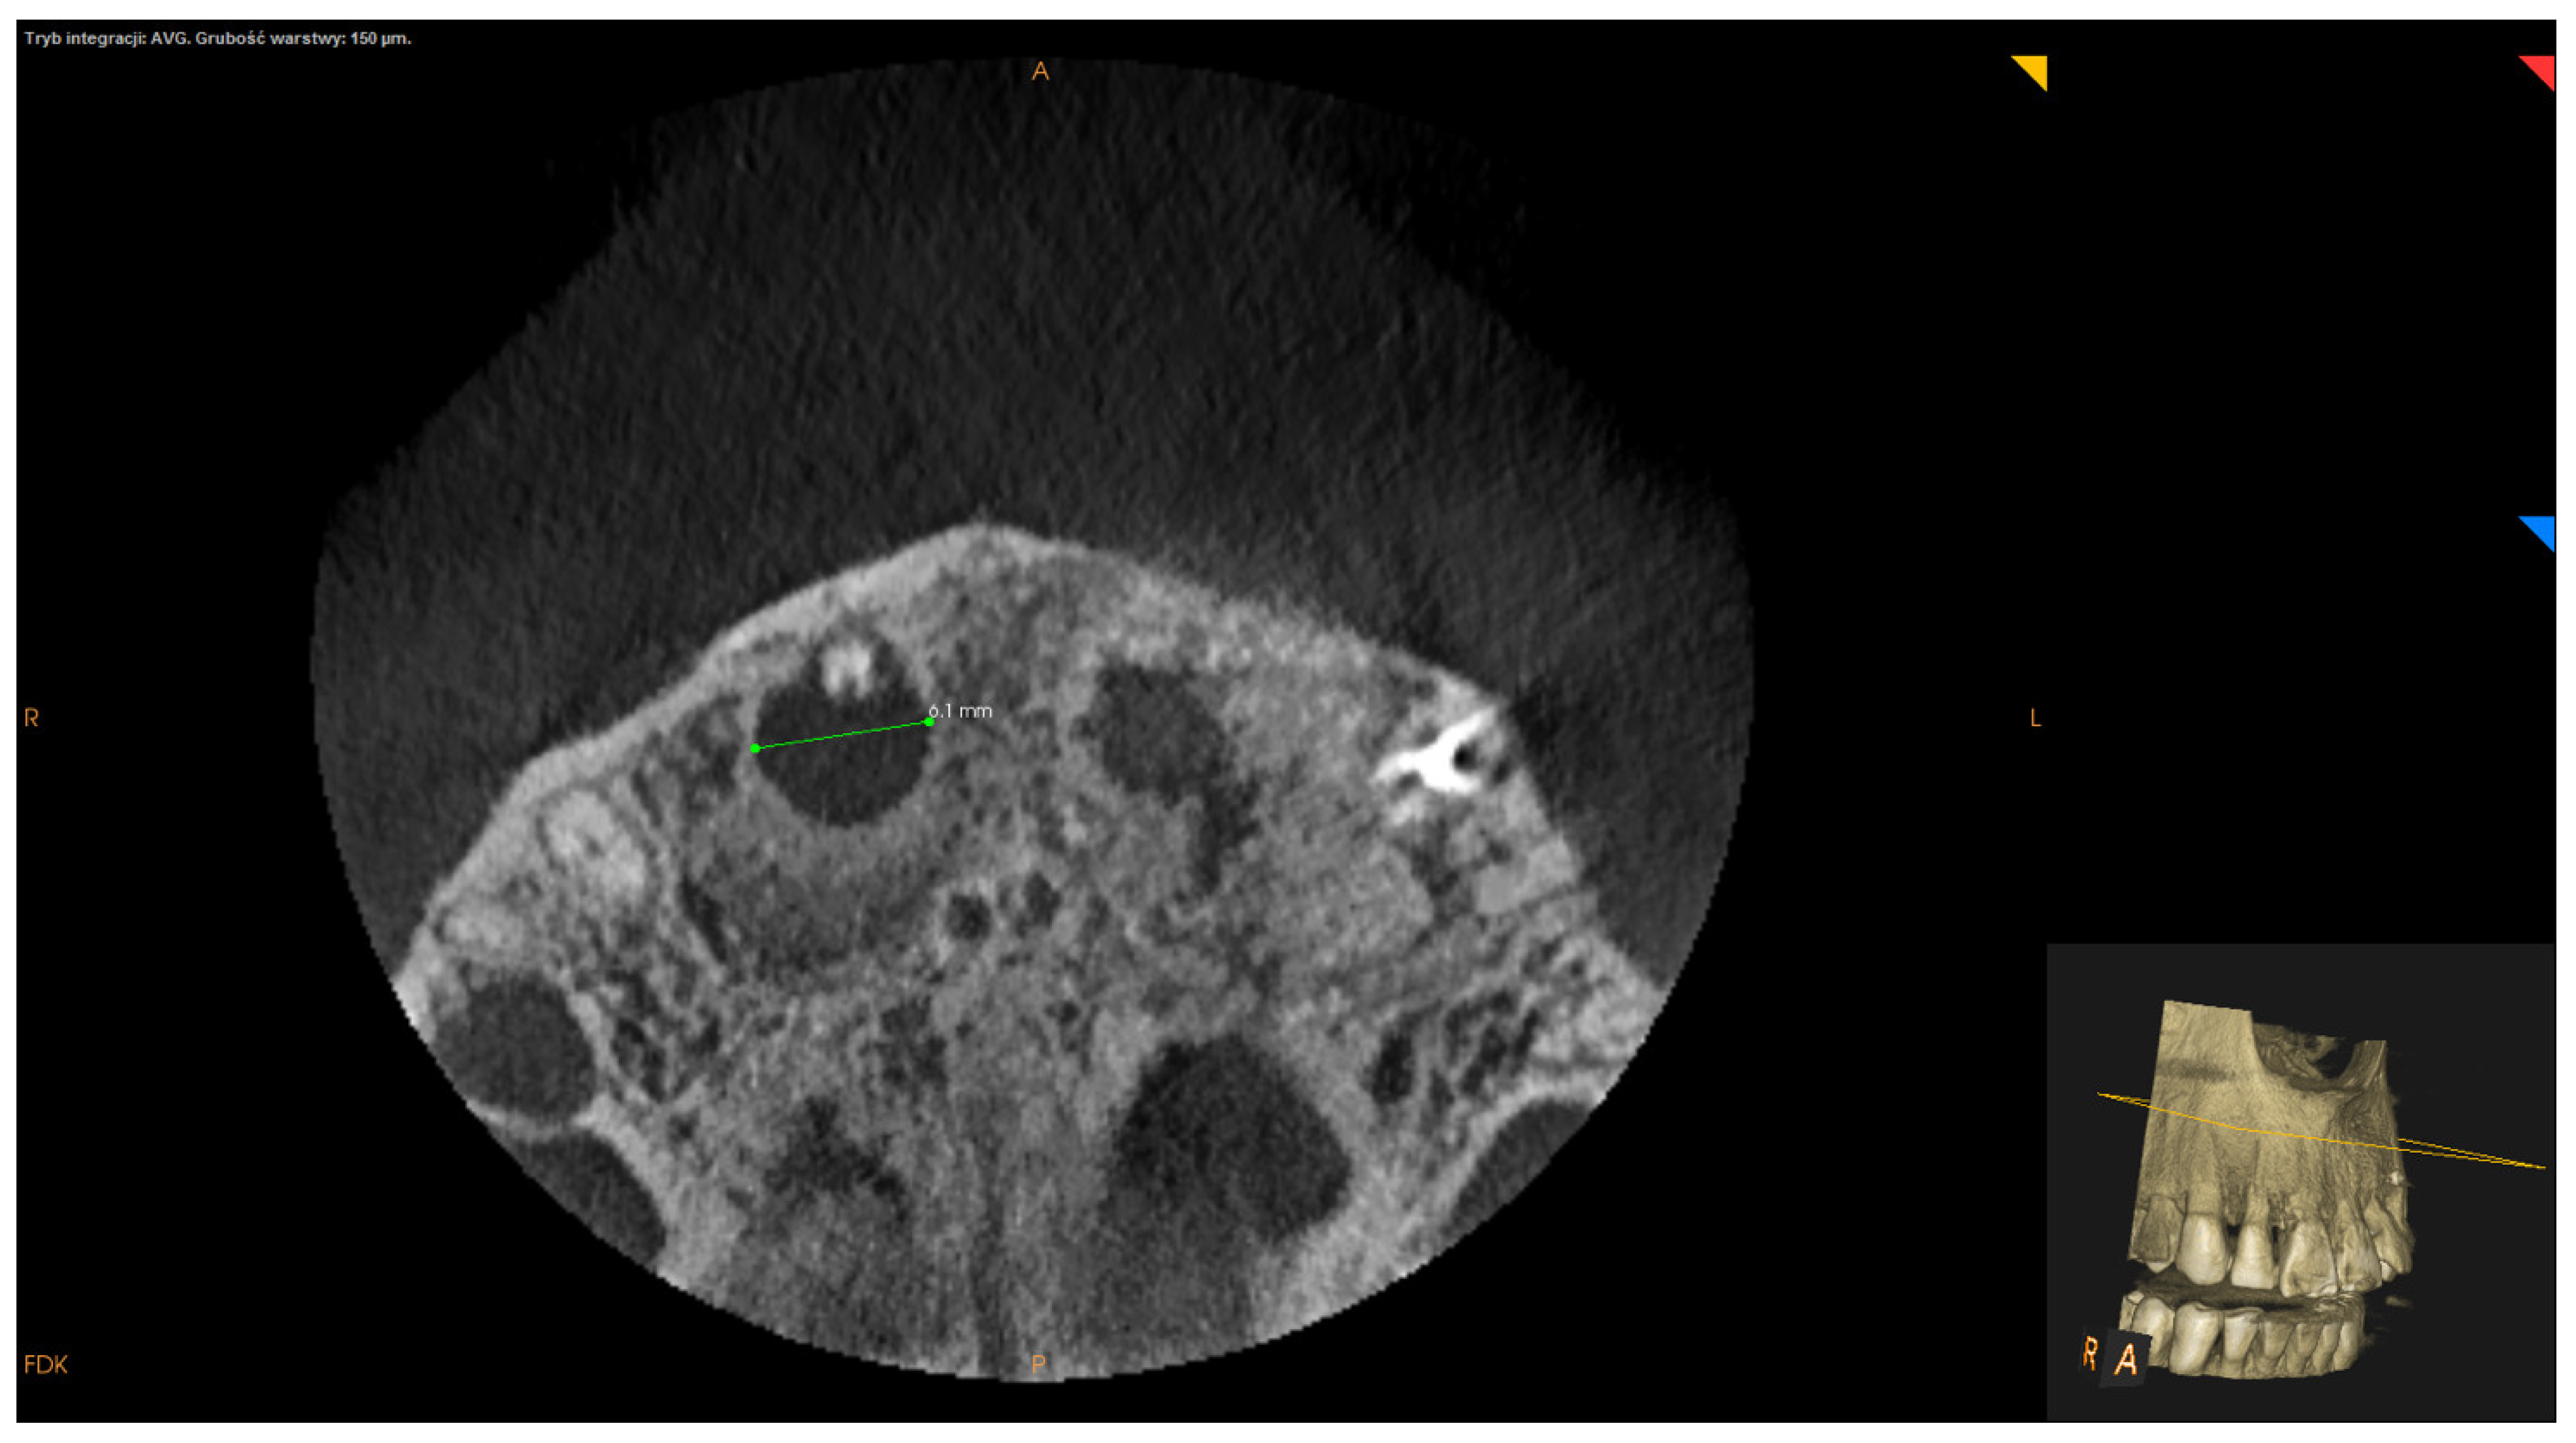

- Mesiodistal maximum diameter (measured in horizontal section) (Figure 4);

| mesiodistal maximum diameter M ± SD: 8.86 ± 4.65 | <8.86 mm | 54 (60.67%) |

| >8.86 mm | 35 (39.33%) | |